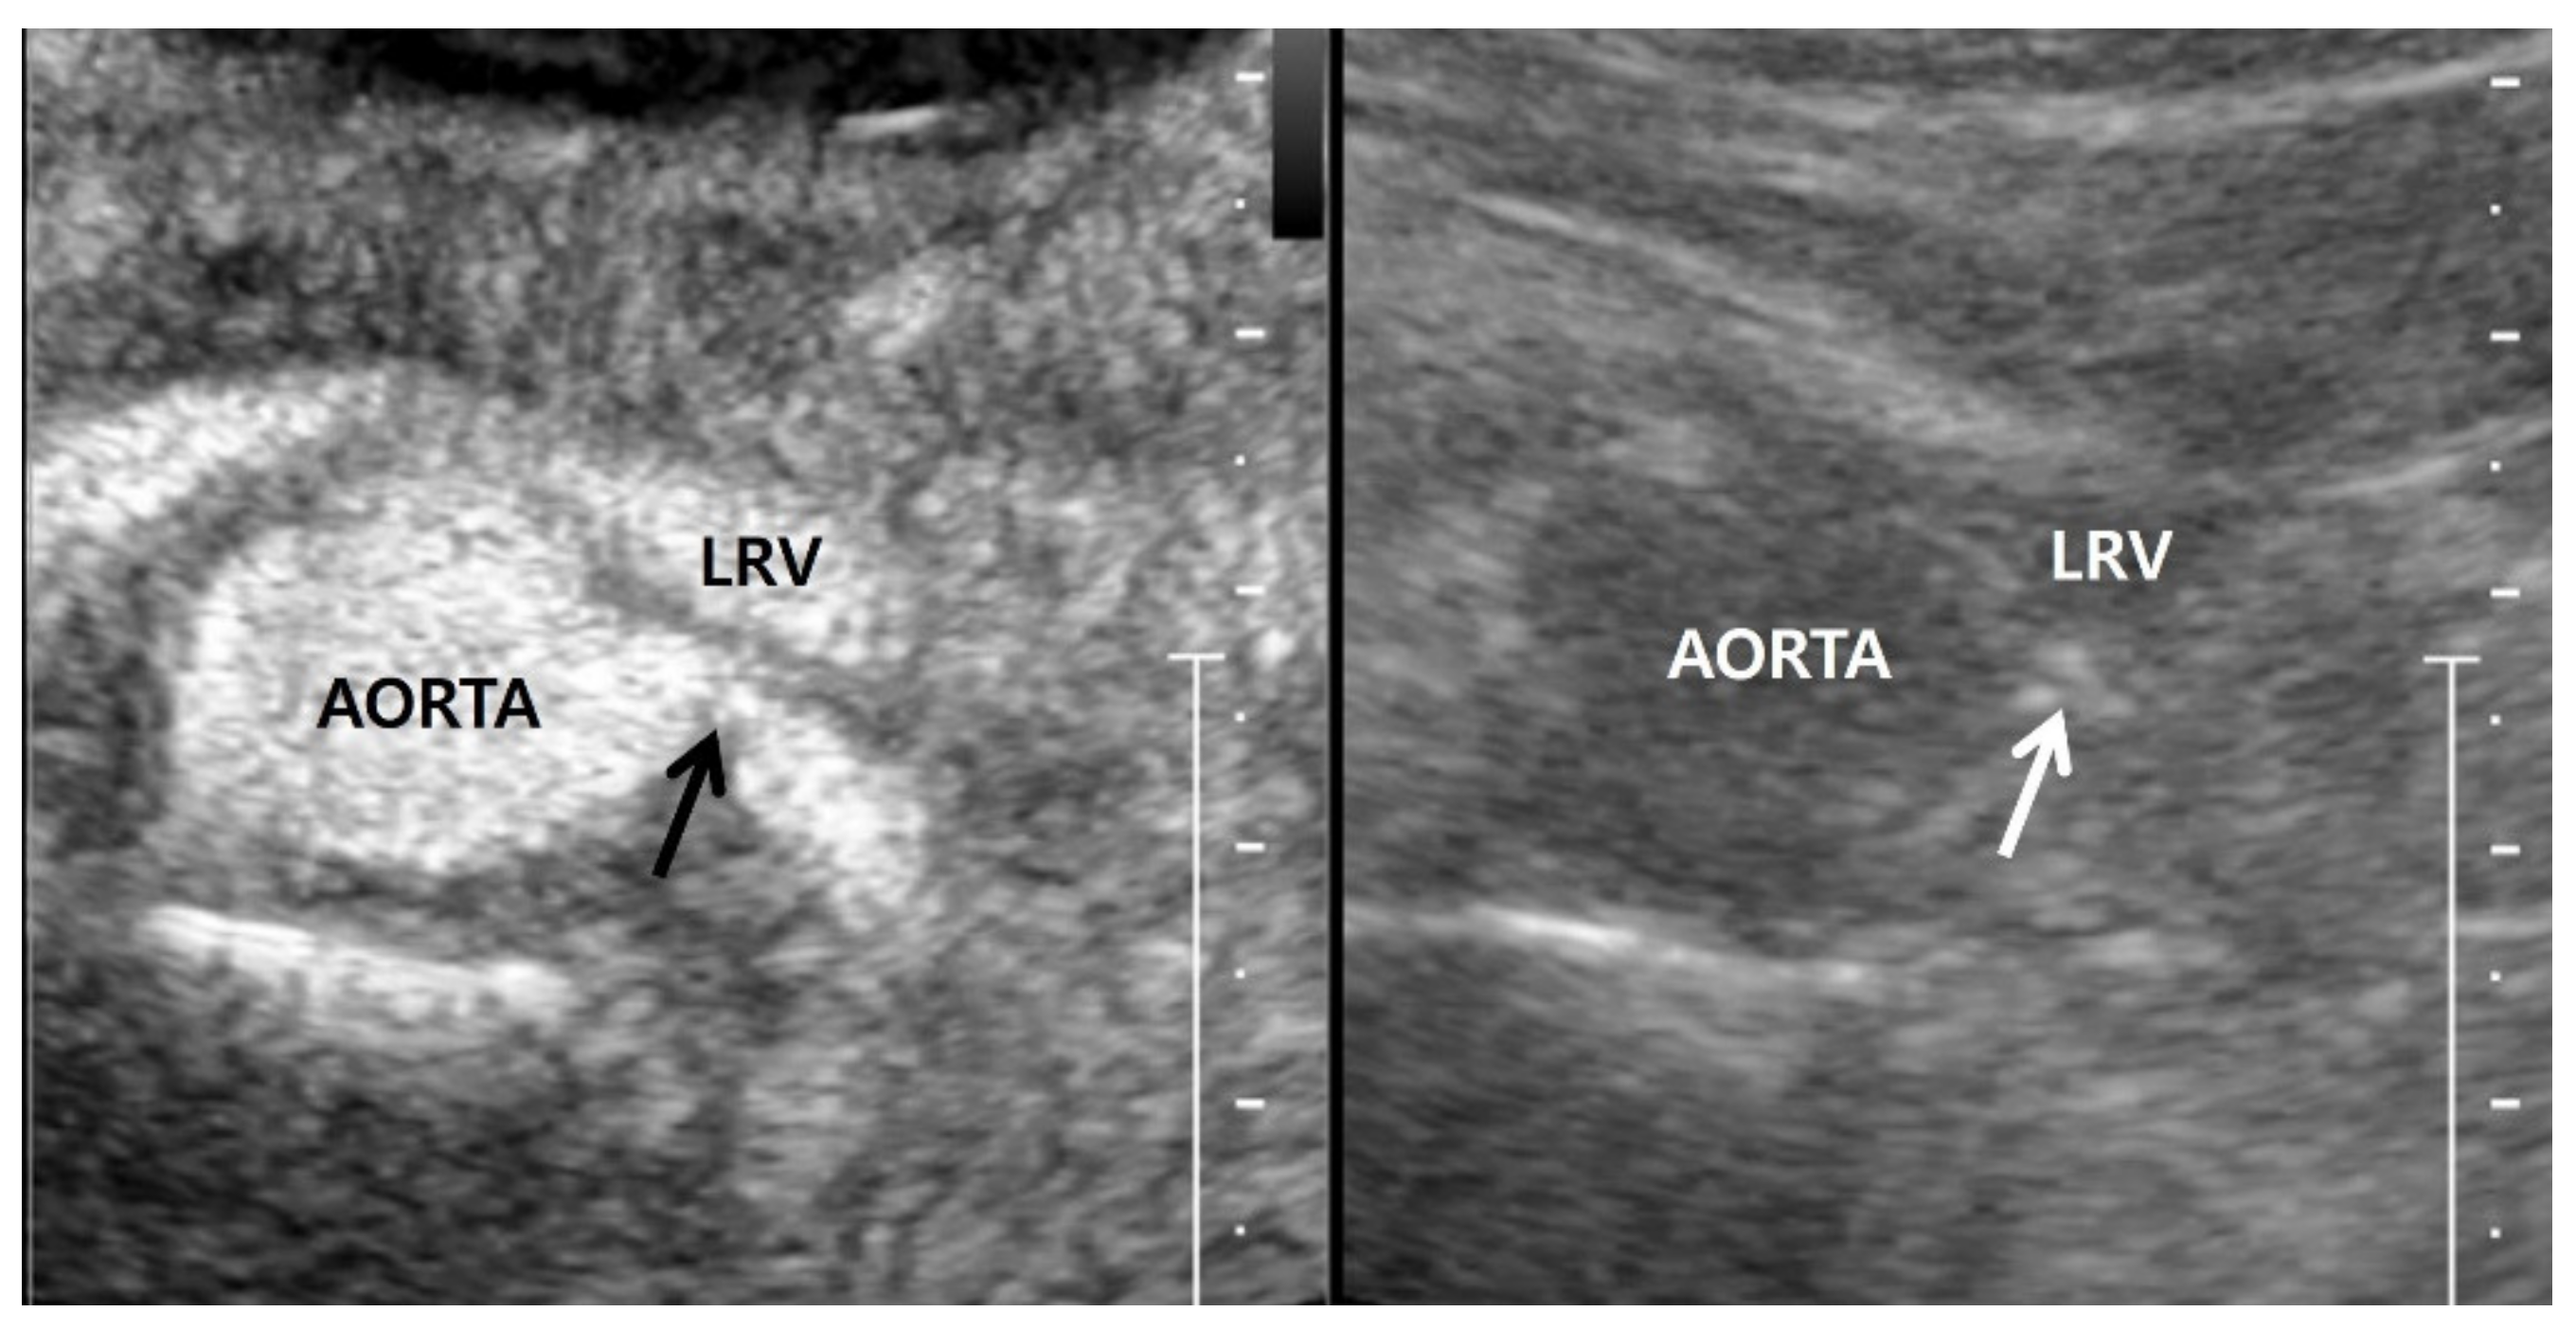

5.1. Gray-Scale US